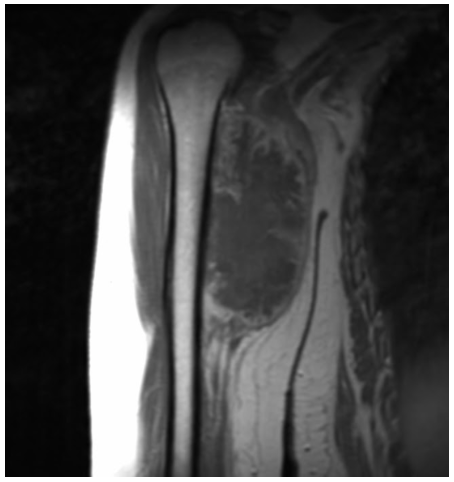

Radiographic imaging is used to help form a diagnosis. These include X-Ray, MRI, CT and Bone Scans.

An example of an MRI is shown.